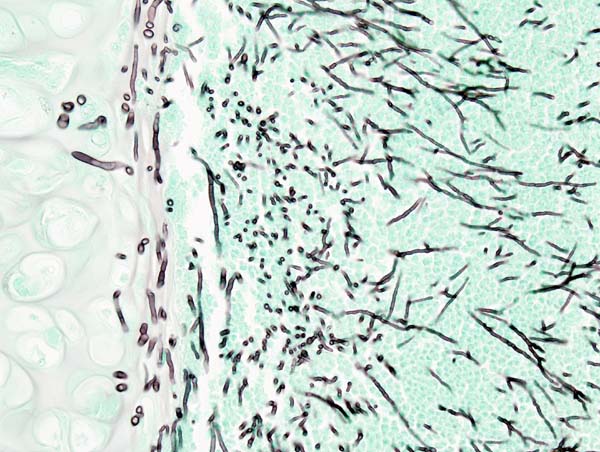

Aspergiloza to infekcja wywołana przez grzyby z rodzaju Aspergillus, które są powszechnie występującymi saprofitycznymi organizmami. Grzyby te można znaleźć w glebie, na roślinach, a także w materiałach organicznych, takich jak pleśń czy resztki roślinne. Aspergiloza jest szczególnie niebezpieczna dla osób z osłabionym układem odpornościowym, takich jak pacjenci po przeszczepach, osoby z chorobami płuc czy osoby przyjmujące leki immunosupresyjne.

Zakażenie aspergiloza może być trudne do zdiagnozowania, ponieważ objawy często przypominają inne choroby płucne. W diagnostyce wykorzystuje się różne metody, w tym badania obrazowe, testy laboratoryjne i biopsje.

Biopsja jest badaniem medycznym powszechnie wykonywanym przez chirurga, radiologa interwencyjnego lub kardiologa interwencyjnego. Proces ten polega na pobraniu próbki komórek lub tkanek do badania w celu określenia obecności lub zakresu choroby. Tkanka jest następnie utrwalana, odwadniana, osadzana, sekcjonowana, barwiona zanim zostanie ogólnie zbadana pod mikroskopem przez patologa; może być również analizowana chemicznie. Biopsje są najczęściej wykonywane w celu uzyskania wglądu w ewentualne stany nowotworowe lub zapalne. >>>